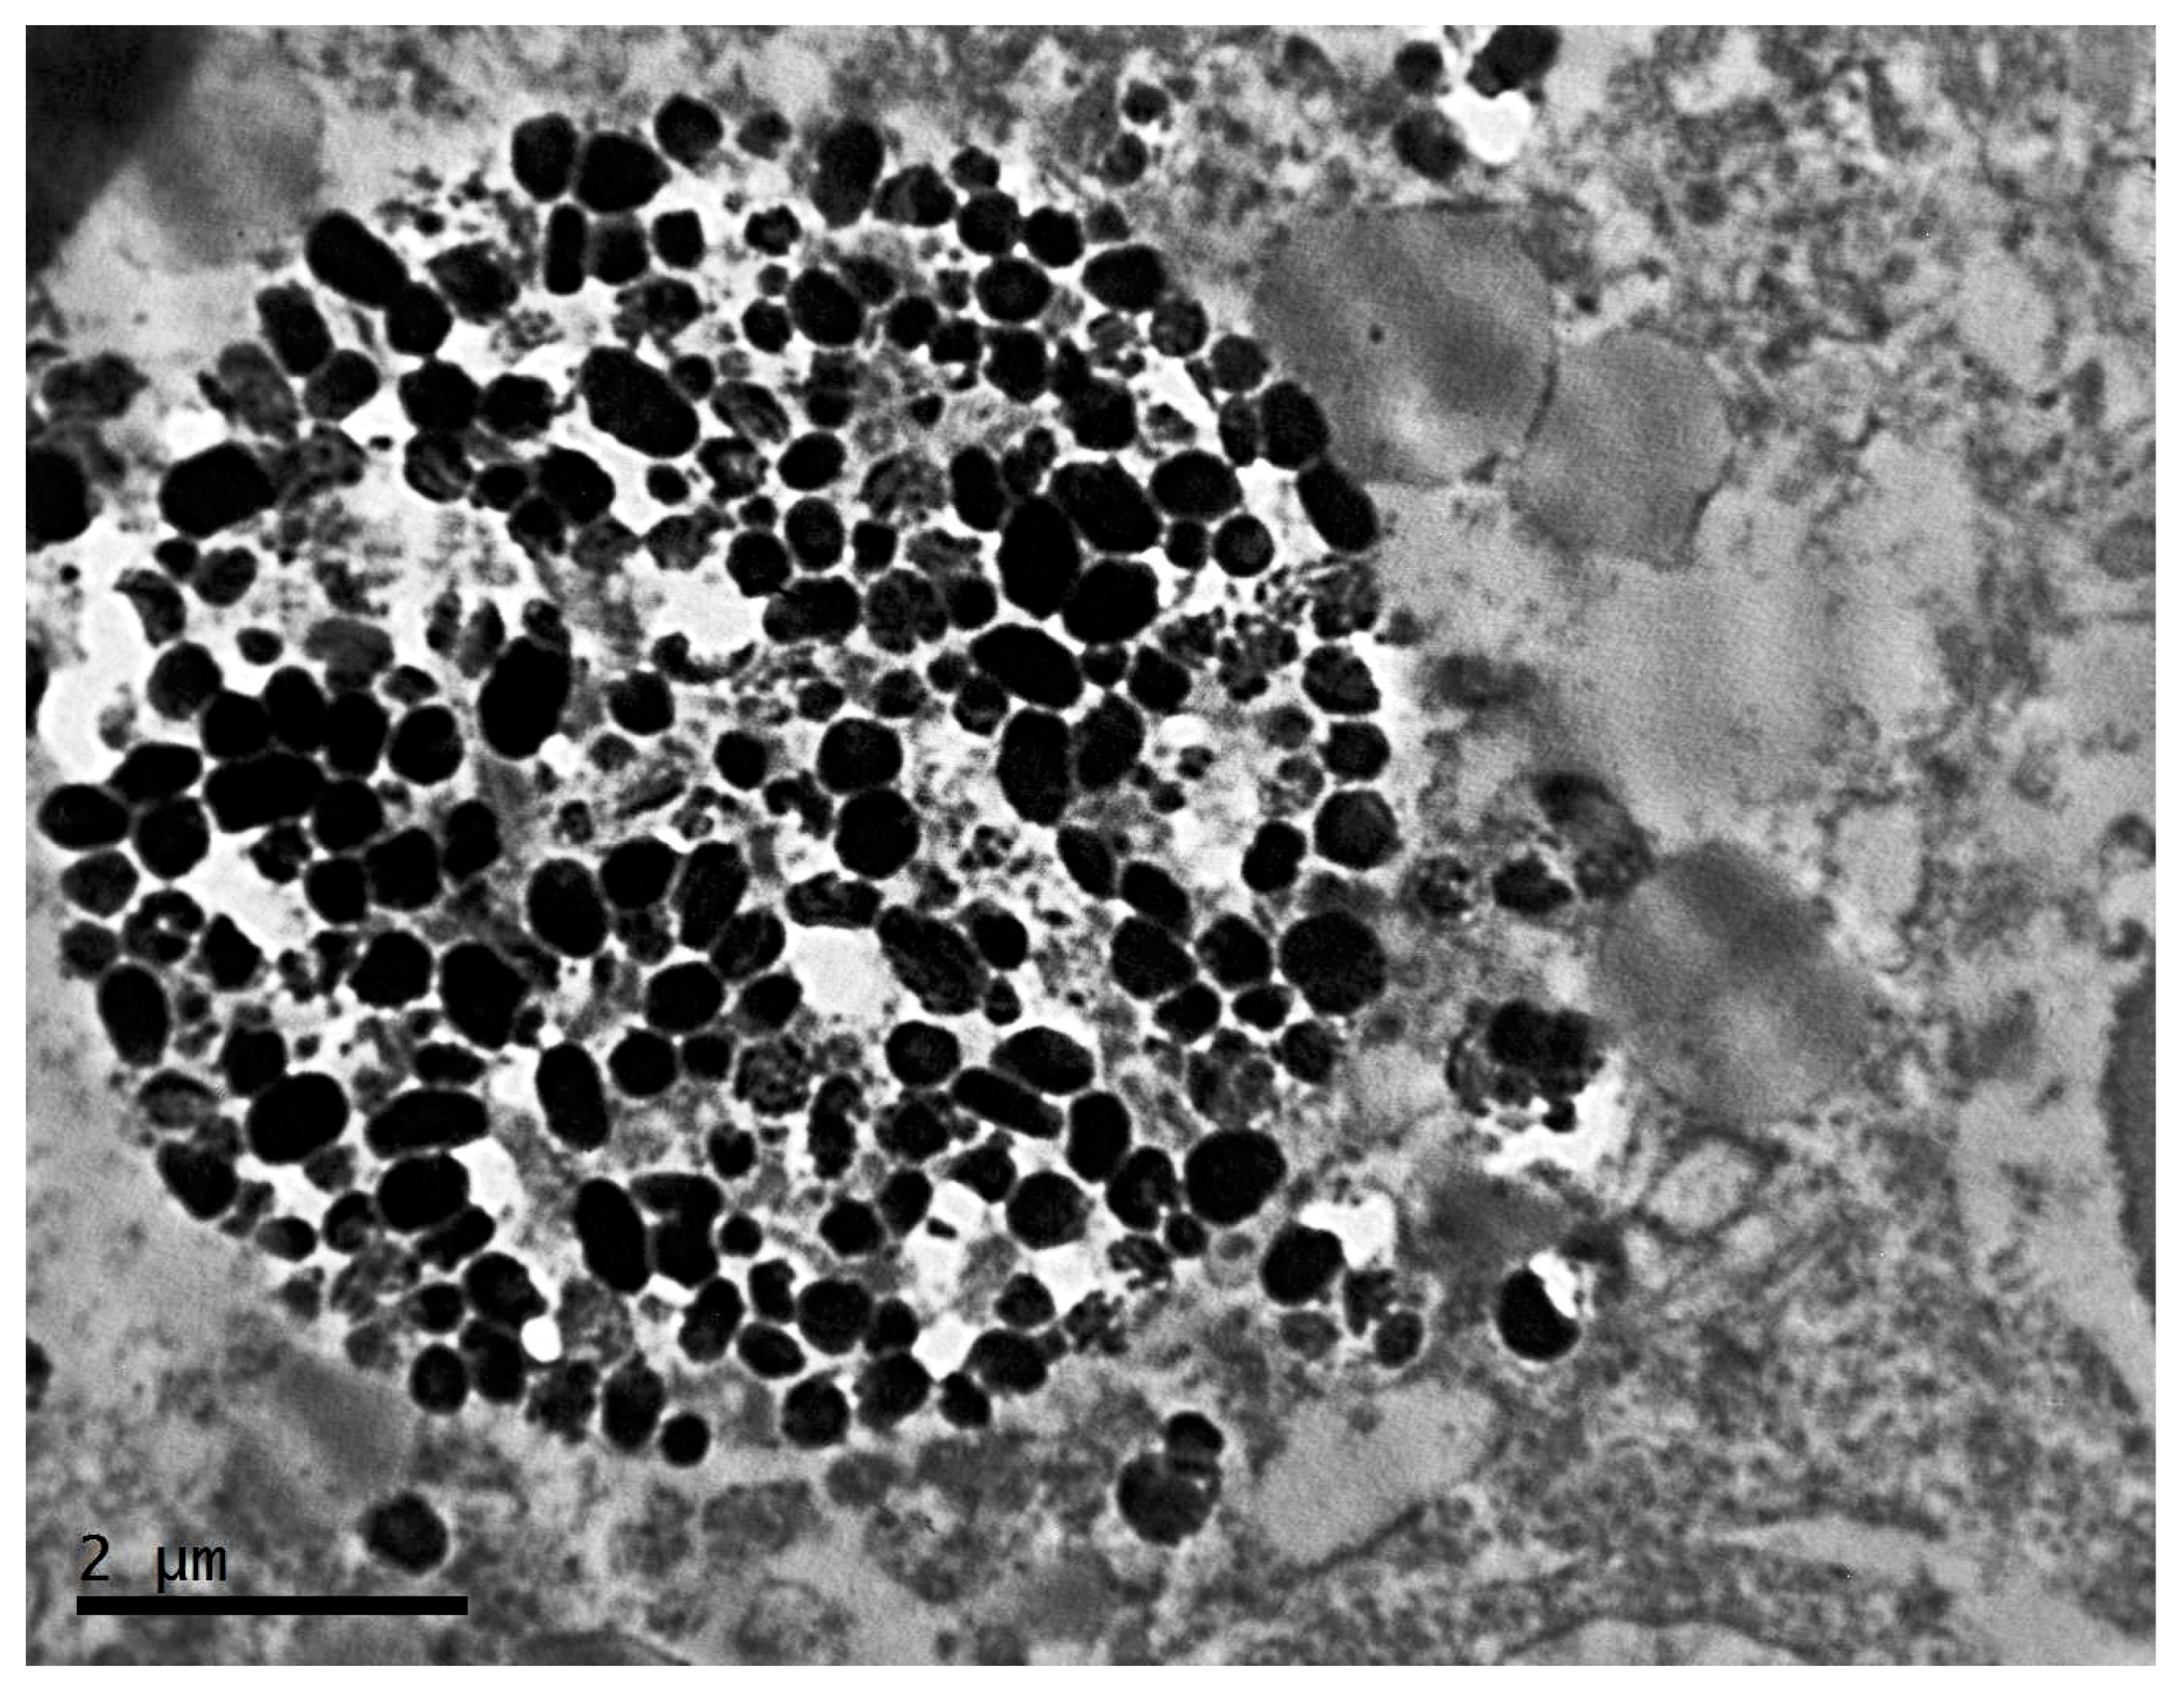

2.2. Ultrastructure of Transplantable Malignant Melanoma B16 in Conditions of Constant Lighting Regime